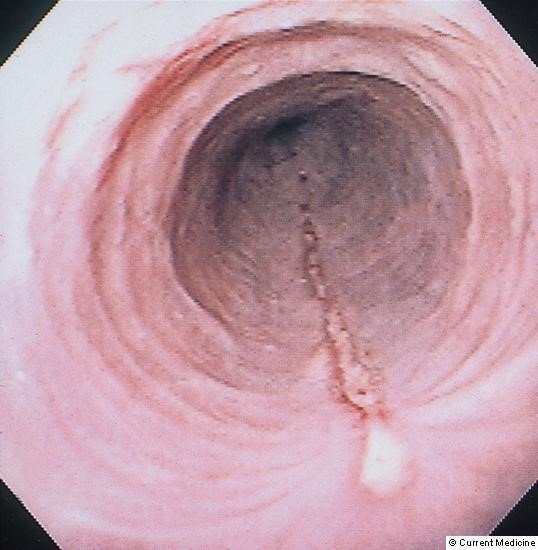

Divertikul QB divarının bir qatının və ya bütün qatlarının kisəşəkilli kənara qabarmasıdır. Divertikulun iç səthi epitel toxuması ilə örtülü olur.

Qida borusu divarının bir qatının və ya bütün qatlarının kisəşəkilli kənara çıxması (qabarması) divertikul adlanır. Divertikulun iç səthi epitel toxuması ilə örtülü olur. Divar zəifliyi və distal hissədə maneə divertikulun əmələ gəlməsində mühüm rol oynayır. Divertikullar qida borusunun yuxarı (Zenker divertikulu), orta və aşağı (epifrenik divertikul) hissələrində çox rast gəlir. Xəstəlik erkən mərhələlərdə asimtomatik ola bilir, böyüdükdə disfagiya, requrgitasiya, ağızdan pis iy gəlməsi əlamətləri ilə büruzə verir. Uzunmüddətli divertikullar iltihab, böyüyüərək ətraf orqanları sıxma, hətta perforasiya törədə bilirlər. Diaqnoz kontrastlı müayinələrlə qoyulur. Müalicə əsasən cərrahidir (divertikulektomiya, distal miotomiya).